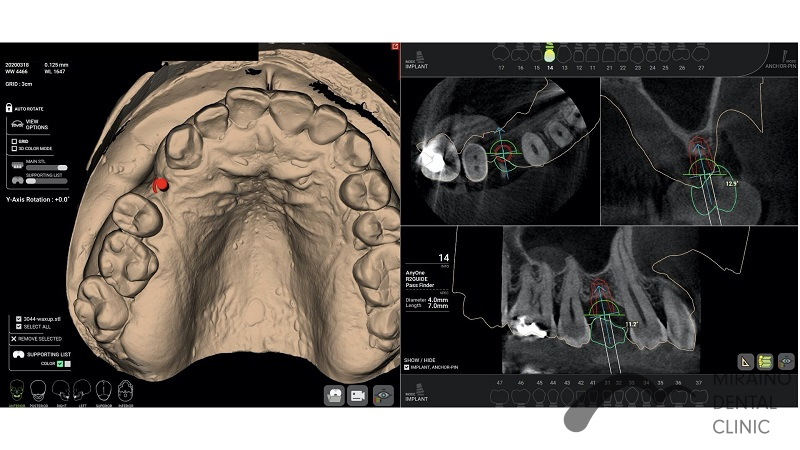

インプラントの症例

Case1

| 施術名 | インプラント |

| 施術の概要 | 10年前ほどに根の先に膿ができて抜歯。 前医では骨が少なくなってしまってインプラントは不可能ということで当院来院。 インプラントOPE時に仮歯まで作成し見た目の回復まで行いました。 その後OPE後3ヶ月で最終の被せ物装着する。 |

| 施術の内容 | インプラントは、従来の入れ歯やブリッジとは違い、天然の歯と同じような強くて、美しい歯を取り戻す治療法です。 失った歯の代わりに人工の歯根を埋め込み、その上に人工の歯を装着。 健康な歯を削ることなく、新しい歯が蘇ります。 2~3か月後に上部構造(歯の部分)を装着してかみ合わせを回復させます。 |

| 1歯あたりの治療費 | 450,000円(10年保証込) 骨が薄く造成が必要な場合は追加費用がかかります。 骨造成:30,000円~100,000円 |

| 考えられるリスク、副作用 | 疼痛・咬合時痛・腫脹や出血などを生じる事があります。 時間経過とともに治ります。 |

| 考えられるリスク、副作用[全てにおいて] | 必ずしもご希望通りの見た目にならない事があります。 |

| 考えられるリスク、副作用[麻酔] | 麻酔を行う場合、腫れやむくみを生じる事があります。 |

| 考えられるリスク、副作用[噛み合わせ] | かみ合わせの変化・違和感が生じる事があります。 |

| 考えられるリスク、副作用[被せ・仮歯] | 強い衝撃を与えると、被せ物が欠けたり割れたり、外れたりする事があります。 仮歯の期間中は仮歯の部分で噛むと破損する場合があります。 |

| 保証について | 治療後10年以内であれば再治療を行います。 喫煙、糖尿病、加齢、清掃不良などメンテナンスが不十分な場合、インプラント周囲炎になる事があります。 10年保証を受けるには当院にて年2回以上のメンテナンスが必要になります。 (メンテナンスはインプラント治療に関わらず、一般的にご自身の歯の場合でも必要であると思われます。) |